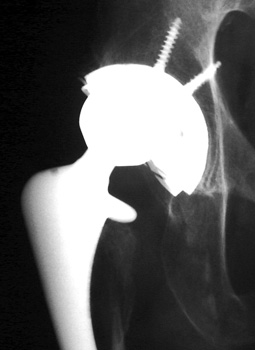

Metal liner dislocation. Model of total hip replacement components positioned with metal  liner dislocated.